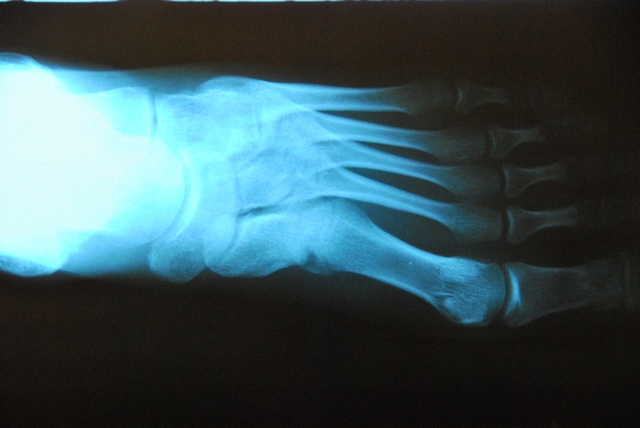

Nie obylo sie bez przygod, bo mistrzowie z peruwianskiego szpitala robiac kontrolny rentgen nie wcelowali w miejsce zlamania i fotke trzeba bylo powtorzyc. Ale najwazniejsze, ze Wasze zyczenia poskutkowaly bo noga sie zrosla ksiazkowo.